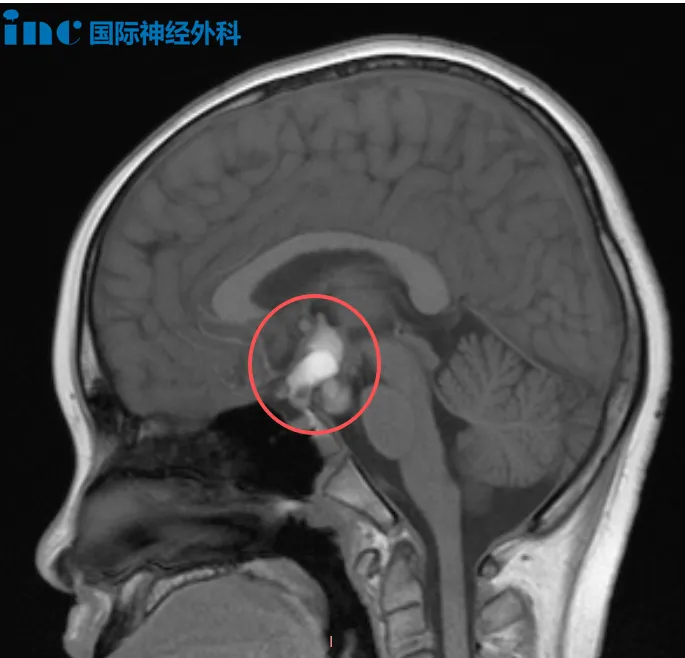

12岁男性颅咽管瘤患者

涛涛今年8月因头痛检出颅咽管瘤,病变尺寸20mm×15mm×27mm,已导致脑干受压后移。“肿瘤压迫视交叉后方视路系统,机械性引起视功能障碍。若手术延迟,压迫可能导致视路进一步损伤,甚至出现永久性视野缺损。”面对中药与偏方疗效不佳、患儿自觉症状加重、生长激素出现问题的情况,巴教授对病情风险评估使家长认识到手术为避免肿瘤恶化、为患儿争取未来的唯一选择。